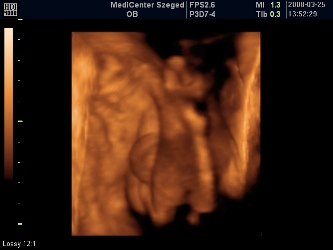

Megjöttünk a 4D-ről! :lol: 40 percet moziztunk, mert Patriknak már a legelején elege lett az egészből, befúrta a fejét a méhlepénybe, rángatta a zsinórt, rúgta a vizsgálófejet, úgyhogy nagyon nem tetszett neki. Azért lett pár kép, de nagyon megsajnáltam a kis drágámat, és én szóltam, hogy mostmár hagyjuk békén. Szerencsére minden a legnagyobb rendben, szép mindene, és befordult (múlt héten még faros volt) és ez a lényeg!!! :lol:

A méretei mostmár bizti, hogy 2 héttel nagyobbak, tehát 30 betöltött hétnek megfelelő, de a vonalzóm mostmár marad, úgyis a bébi dönti el, hogy mikor jön pontosan (de eszerint június 1-én) :lol:

A súlya: 1320 gram :shock:

Rakok képeket: kettő pofis, egy zacsis. :oops: :lol: